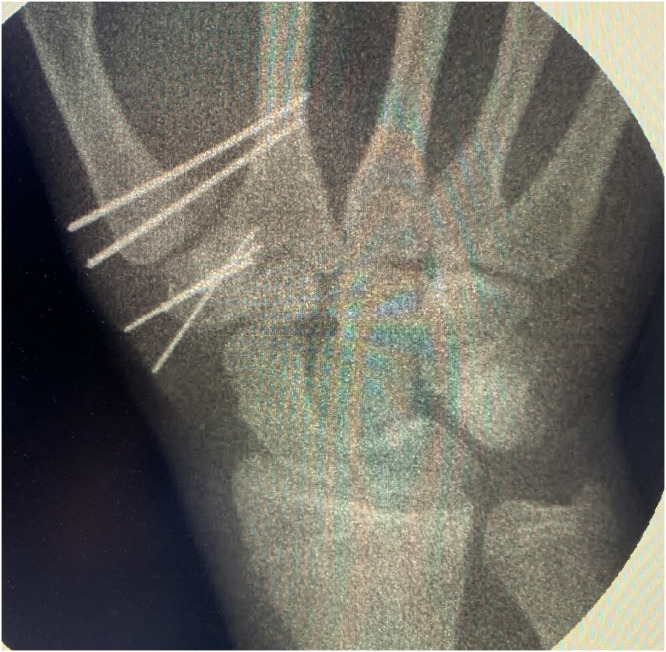

Figure 2.

Fluoroscopic view following trapezium fixation and reduction of the thumb metacarpal base with transfixation to the second metacarpal.